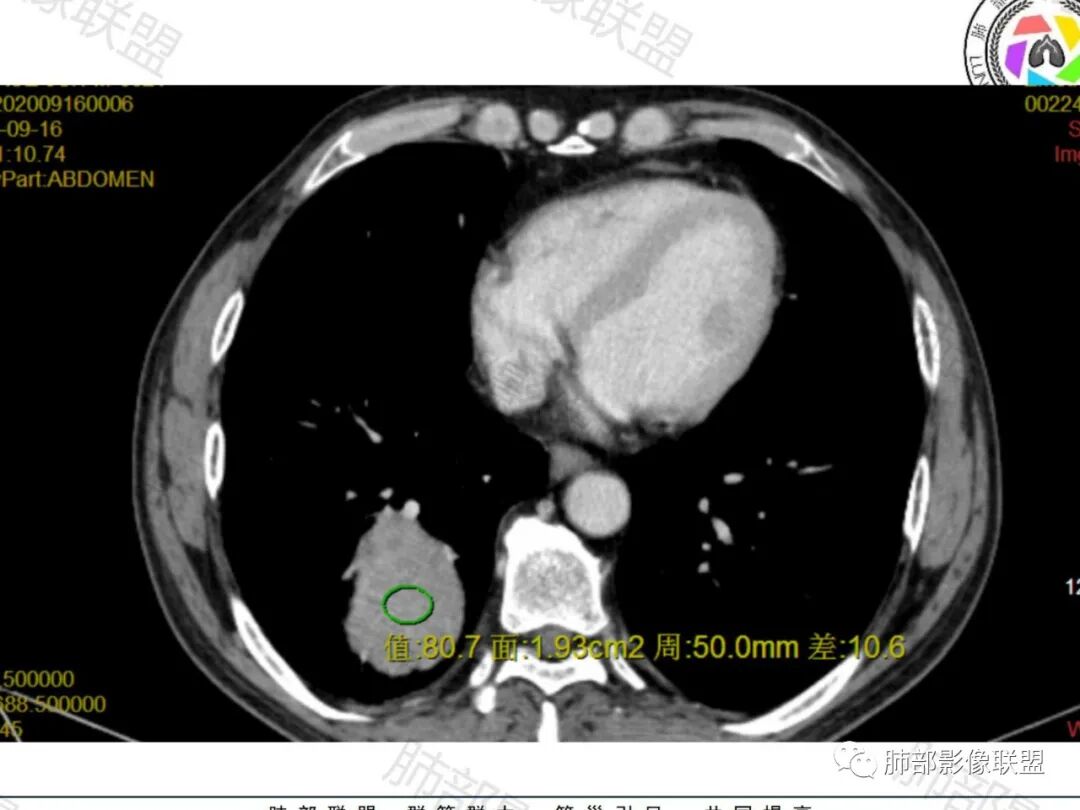

右肺下叶一类圆形肿块影,内缘边缘光滑,外缘边界模糊,可见磨玻璃影,整体以彭隆为主,部分边缘包绕支气管,平扫密度尚均匀,增强后不均匀强化,部分与膈肌黏连,临床,62岁男性,无症状,考虑恶性:腺癌,鳞癌,神经内分泌癌,肉瘤

老年人,偶然发现,右肺下叶类圆形软组织占位,密度较均匀,病灶边缘光滑,无毛刺分叶,支气管血管受挤压向外移位,增强病灶强化较均匀。考虑恶性肿瘤,外向内生长,肉瘤,肉瘤样癌,癌肉瘤,其次神经内分泌癌。

老年男性,右肺下叶软组织肿物,整体外形光整,周围组织推挤,可见血管贴边,貌似又有血管进入,整体强化均匀,考虑良性可能大,硬化性肺细胞瘤?鉴别sft

老年男性,偶然发现,说明平时没有症状,边缘光整,血管贴边,整体强化均匀,倾向于良性或者低度恶性(PSP?类癌?)

老年男性,肿瘤标志物高,右肺占位,边界清楚,内部密度均匀,坏死不明显,无明显分叶,血管贴边,考虑PSP,老年男性,肿块大,需鉴别恶性,肉瘤样癌?高分化鳞癌?

男性,62,胆结石入院胸部CT偶然发现占位。肿标稍增高,右肺下叶胸膜下肿块,边缘尚清,密度较均匀,增强明显强化,血管贴边,空气新月征?静脉期可见低强化区,首先考虑PSP,鉴别肉瘤样癌及神经内分泌肿瘤

老年男性,右肺下叶肿块,边缘光整,血管贴边,部分血管进入,整体强化尚均匀,考虑大细胞癌,鉴别PSP、SFT

右肺下叶类圆形软组织肿块,病灶边缘光滑,无明显毛刺分叶,支气管受压推移,血管贴边,部分血管进入病灶,增强病灶强化不均匀,内可见低密度,病灶与右侧膈肌分界不清,考虑神经内分泌肿瘤,大细胞癌。鉴别PSP

老年男性,肿瘤标志物高,右肺下叶类圆形肿块,宽基底与胸膜相连,边缘光整,密度均匀,周围气管及血管受压推移,延迟强化,其内见纤细血管,似有小低密度灶,首先考虑间叶组织恶性肿瘤,良性平滑肌瘤、纤维瘤不除外

患者中老年男性,检查发现右下肺占位。查肺癌标记物稍有升高。血常规白细胞计数稍降低。胸部CT:右肺下叶后基底段类圆形肿块,边缘光滑,边界清楚,周边见气管受压扩张,增强轻度强化,内见点状低密度影,见血管贴边。综合考虑良性过低度恶性病变,PSP可能,其它恶性肿瘤待排。

支气管,血管均受压推移,类圆形占位,无分叶,无毛刺,光滑表面,明显均匀强化,倾向于psp,鉴别错构瘤,肉瘤,肉瘤样癌,类癌等神经内分泌肿瘤,转移,imt。

老年男性,右肺下叶软组织肿块,边缘光滑,血管和支气管贴边,肿块与膈肌分界不清,增强后不均匀强化,可见点片状低密度影,考虑良性或低度恶性肿瘤,psp,神经内分泌肿瘤

右肺下叶大肿块,血管贴边,部分小分支进入肿块内,密度略欠均匀,边缘总体光滑,支气管关系不明确,老年人,总体考虑恶性,nse高,首先考虑神经内分泌癌,鉴别肉瘤,转移瘤

右下肺大团块,边界较清,病灶内有血管影,小灶低密度,胸膜下脂肪清晰,需要薄层确定肺血管有没穿行,疾病谱:神经内分泌癌(大 类),SFT,PSP,肉瘤样癌,间叶肿瘤,考虑神经内分泌癌(大 类)>sft>psp>肉瘤样癌

老年男性,NSE高。右肺下叶软组织肿块,平扫密度均匀,增强后不均匀强化,其内似可见小血管影。肿块边缘光滑,无分叶无毛刺,血管和支气管贴边。考虑神经内分泌肿瘤,鉴别:psp

老年男性,检查发现右下肺占位。CT:右肺下叶一类圆形肿块影,膨隆,无分叶,边缘基本光滑,近端支气管推挤狭窄,与胸膜夹角为锐角,增强见不均匀强化,未见坏死,近端见血管贴边,胸壁脂肪间隙清楚。考虑良性病变——PSP可能性大。鉴别神经内分泌癌、肉瘤、SFT。

右肺下叶软组织肿块,边缘光滑,临近血管受压变形且增粗,增强后见斑片状低强化区,界不清,实性部分见条状血管影,边缘光滑,考虑PSP可能,肿块与支气管关系不密切,腺癌,腺鳞癌不符合,肿块内增强后血管走形自然,间叶组织起源肉瘤不符

有意思的病例,男性,右肺下叶肿块,强化中等,血管贴边,肿标高,考虑低度恶性肿瘤,神经内分泌肿瘤,类癌最可能,别的感觉都要往后放,PSP,我三十五例病例,男性只有3例,比例太低了,而且强化幅度也偏低,而且肿瘤标志物好几个高的,只敢放第二位了

右肺下叶肿块,呈外带大内带小的椭圆形改变(内带受支气管及血管挤压原因),边缘光滑,无分叶毛刺,支气管受压,增强后,均匀延迟强化,动脉期见血管贴边,静脉期内部瘤样血管强化区,相邻胸膜无侵犯,纵隔无淋巴结肿大,符合PSP,不鉴别。

老年男性,肿瘤标志物高,右下肺占位性病变,密度均匀,其内无明显坏死,均匀强化,无毛刺分叶,考虑硬化性肺细胞瘤,鉴别肉瘤样癌

老年男性,右肺下叶肿块,边界光滑,血管贴边,部分小分支进入,肿块内可见增粗血管,肿瘤指标偏高,总体考虑恶性,不典型类癌?大细胞癌?鉴别PSP。

胸部CT:右肺下叶一类圆形肿块影,边界清楚,大部分边缘光滑、外缘边界模糊,邻近支气管推移、血管贴边,病灶内可见分枝状血管,平扫密度尚均匀,增强后大部分均匀延迟强化,部分与膈肌黏连、尾征?考虑:类Ca>PSP>SFT。鉴别肉瘤样Ca,CD等。

肿块位于周围(起自细支气管呼吸道上皮),均匀膨胀生长(符合良性的生长特点),病灶内部大部分密度较均匀,部分小低密度不强化区(囊变),增强强化较明显,边缘血管增粗贴边,临近支气管受压,支持PSP。